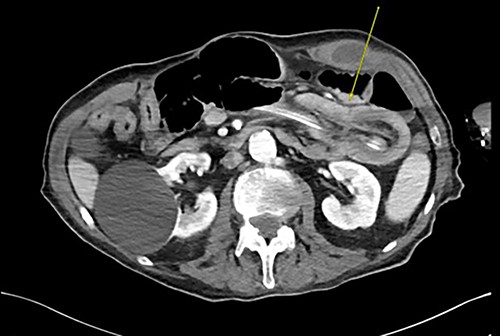

Three weeks later, he presented with a JT obstruction. Multiple attempts using carbonated fluids, enzymes and mechanical brushing failed to clear the obstruction. A computerized tomography of the abdomen and pelvis (CTAP) confirmed the position of the JT and demonstrated telescoping of a long 17 cm segment of jejunum starting from the tip of the JT as lead point (Fig. 1). The JT was removed in hopes of resolution. However, repeat CTAP showed persistent intussusception with mesenteric fat stranding, and possible intestinal ischemia (Fig. 2).

CT abdomen and pelvis revealing telescoping of J-tube (yellow arrow).